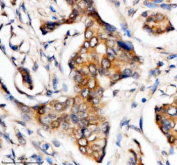

Immunohistochemical staining of MTMR3 using anti-MTMR3 antibody. MTMR3 was detected in a paraffin-embedded section of human breast cancer tissue. Heat mediated antigen retrieval was performed in EDTA buffer (pH 8.0, epitope retrieval solution). The tissue section was blocked with 10% goat serum. The tissue section was then incubated with 2 ug/ml rabbit anti-MTMR3 antibody overnight at 4oC. Peroxidase Conjugated Goat Anti-rabbit IgG was used as secondary antibody and incubated for 30 minutes at 37oC. The tissue section was developed using an HRP secondary and DAB substrate.